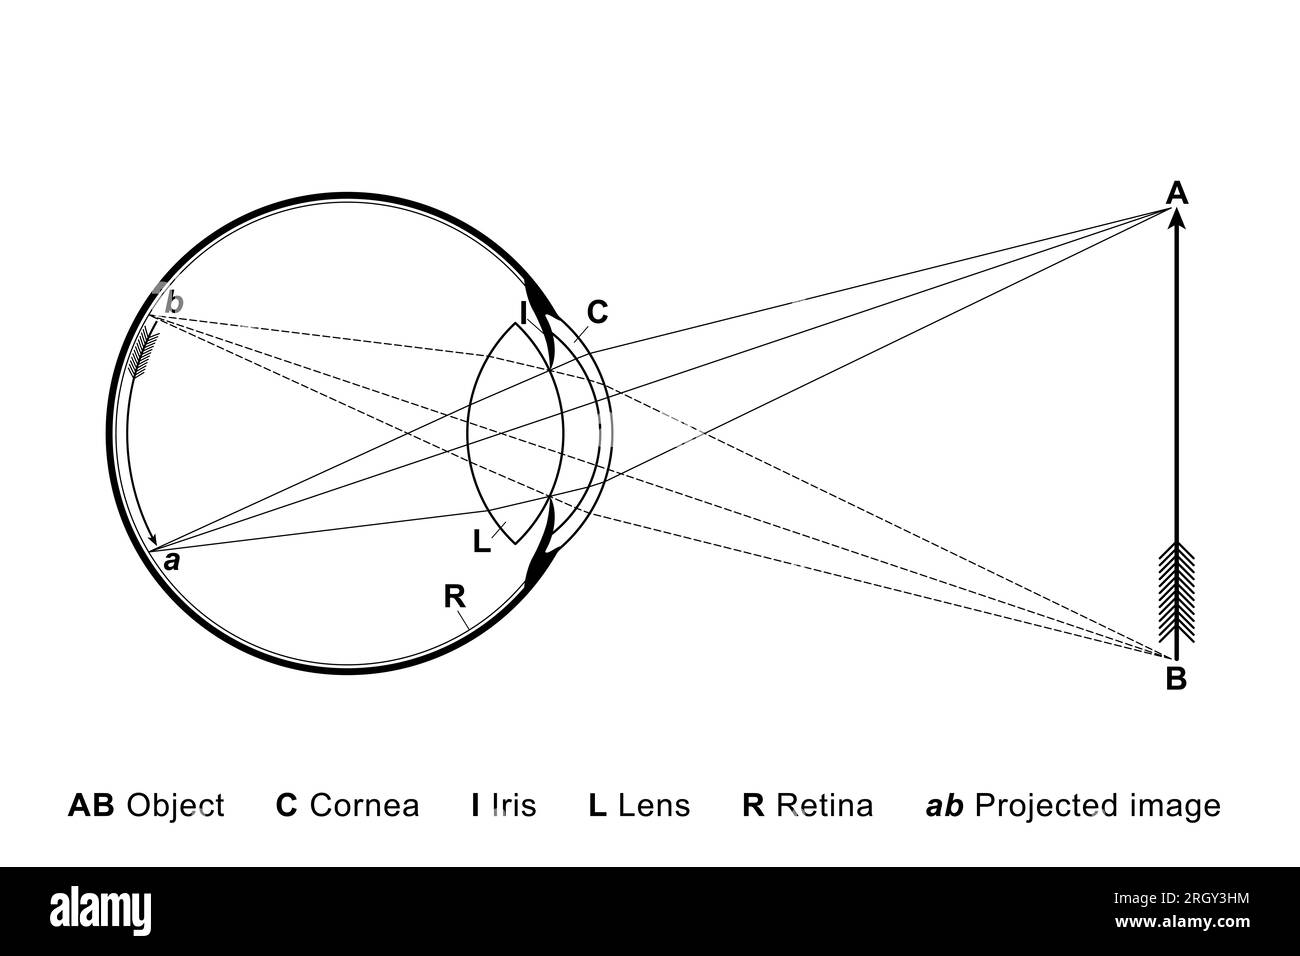

L'œil comme caméra. Globe oculaire avec cornée et lentille, où les rayons subissent une réfraction. L'objet AB est projeté à l'envers sur la rétine. Banque D'Imageshttps://www.alamyimages.fr/image-license-details/?v=1https://www.alamyimages.fr/l-oeil-comme-camera-globe-oculaire-avec-cornee-et-lentille-ou-les-rayons-subissent-une-refraction-l-objet-ab-est-projete-a-l-envers-sur-la-retine-image561161824.html

L'œil comme caméra. Globe oculaire avec cornée et lentille, où les rayons subissent une réfraction. L'objet AB est projeté à l'envers sur la rétine. Banque D'Imageshttps://www.alamyimages.fr/image-license-details/?v=1https://www.alamyimages.fr/l-oeil-comme-camera-globe-oculaire-avec-cornee-et-lentille-ou-les-rayons-subissent-une-refraction-l-objet-ab-est-projete-a-l-envers-sur-la-retine-image561161824.htmlRF2RGY3HM–L'œil comme caméra. Globe oculaire avec cornée et lentille, où les rayons subissent une réfraction. L'objet AB est projeté à l'envers sur la rétine.